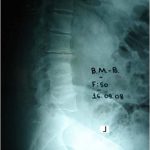

Εικόνα : Μετωπιαία ακτινογραφία οσφυϊκής μοίρας του Ω.Ω. 77 ετών ο οποίος αιτιάται για χρόνιο συνεχή πόνο στην περιοχή αυτή που οφείλετο σε εκφυλιστική σκολίωση που συσχετίζετο με εκφύλιση των σπονδυλικών διαρθρώσεων και των μεσοσπονδύλιων δίσκων. Υπό ακτινοσκοπικό έλεγχο πραγματοποιήθηκε διήθηση των σπονδυλικών διαθρώσεων με κορτιζόνη και τοπικό αναισθητικό.